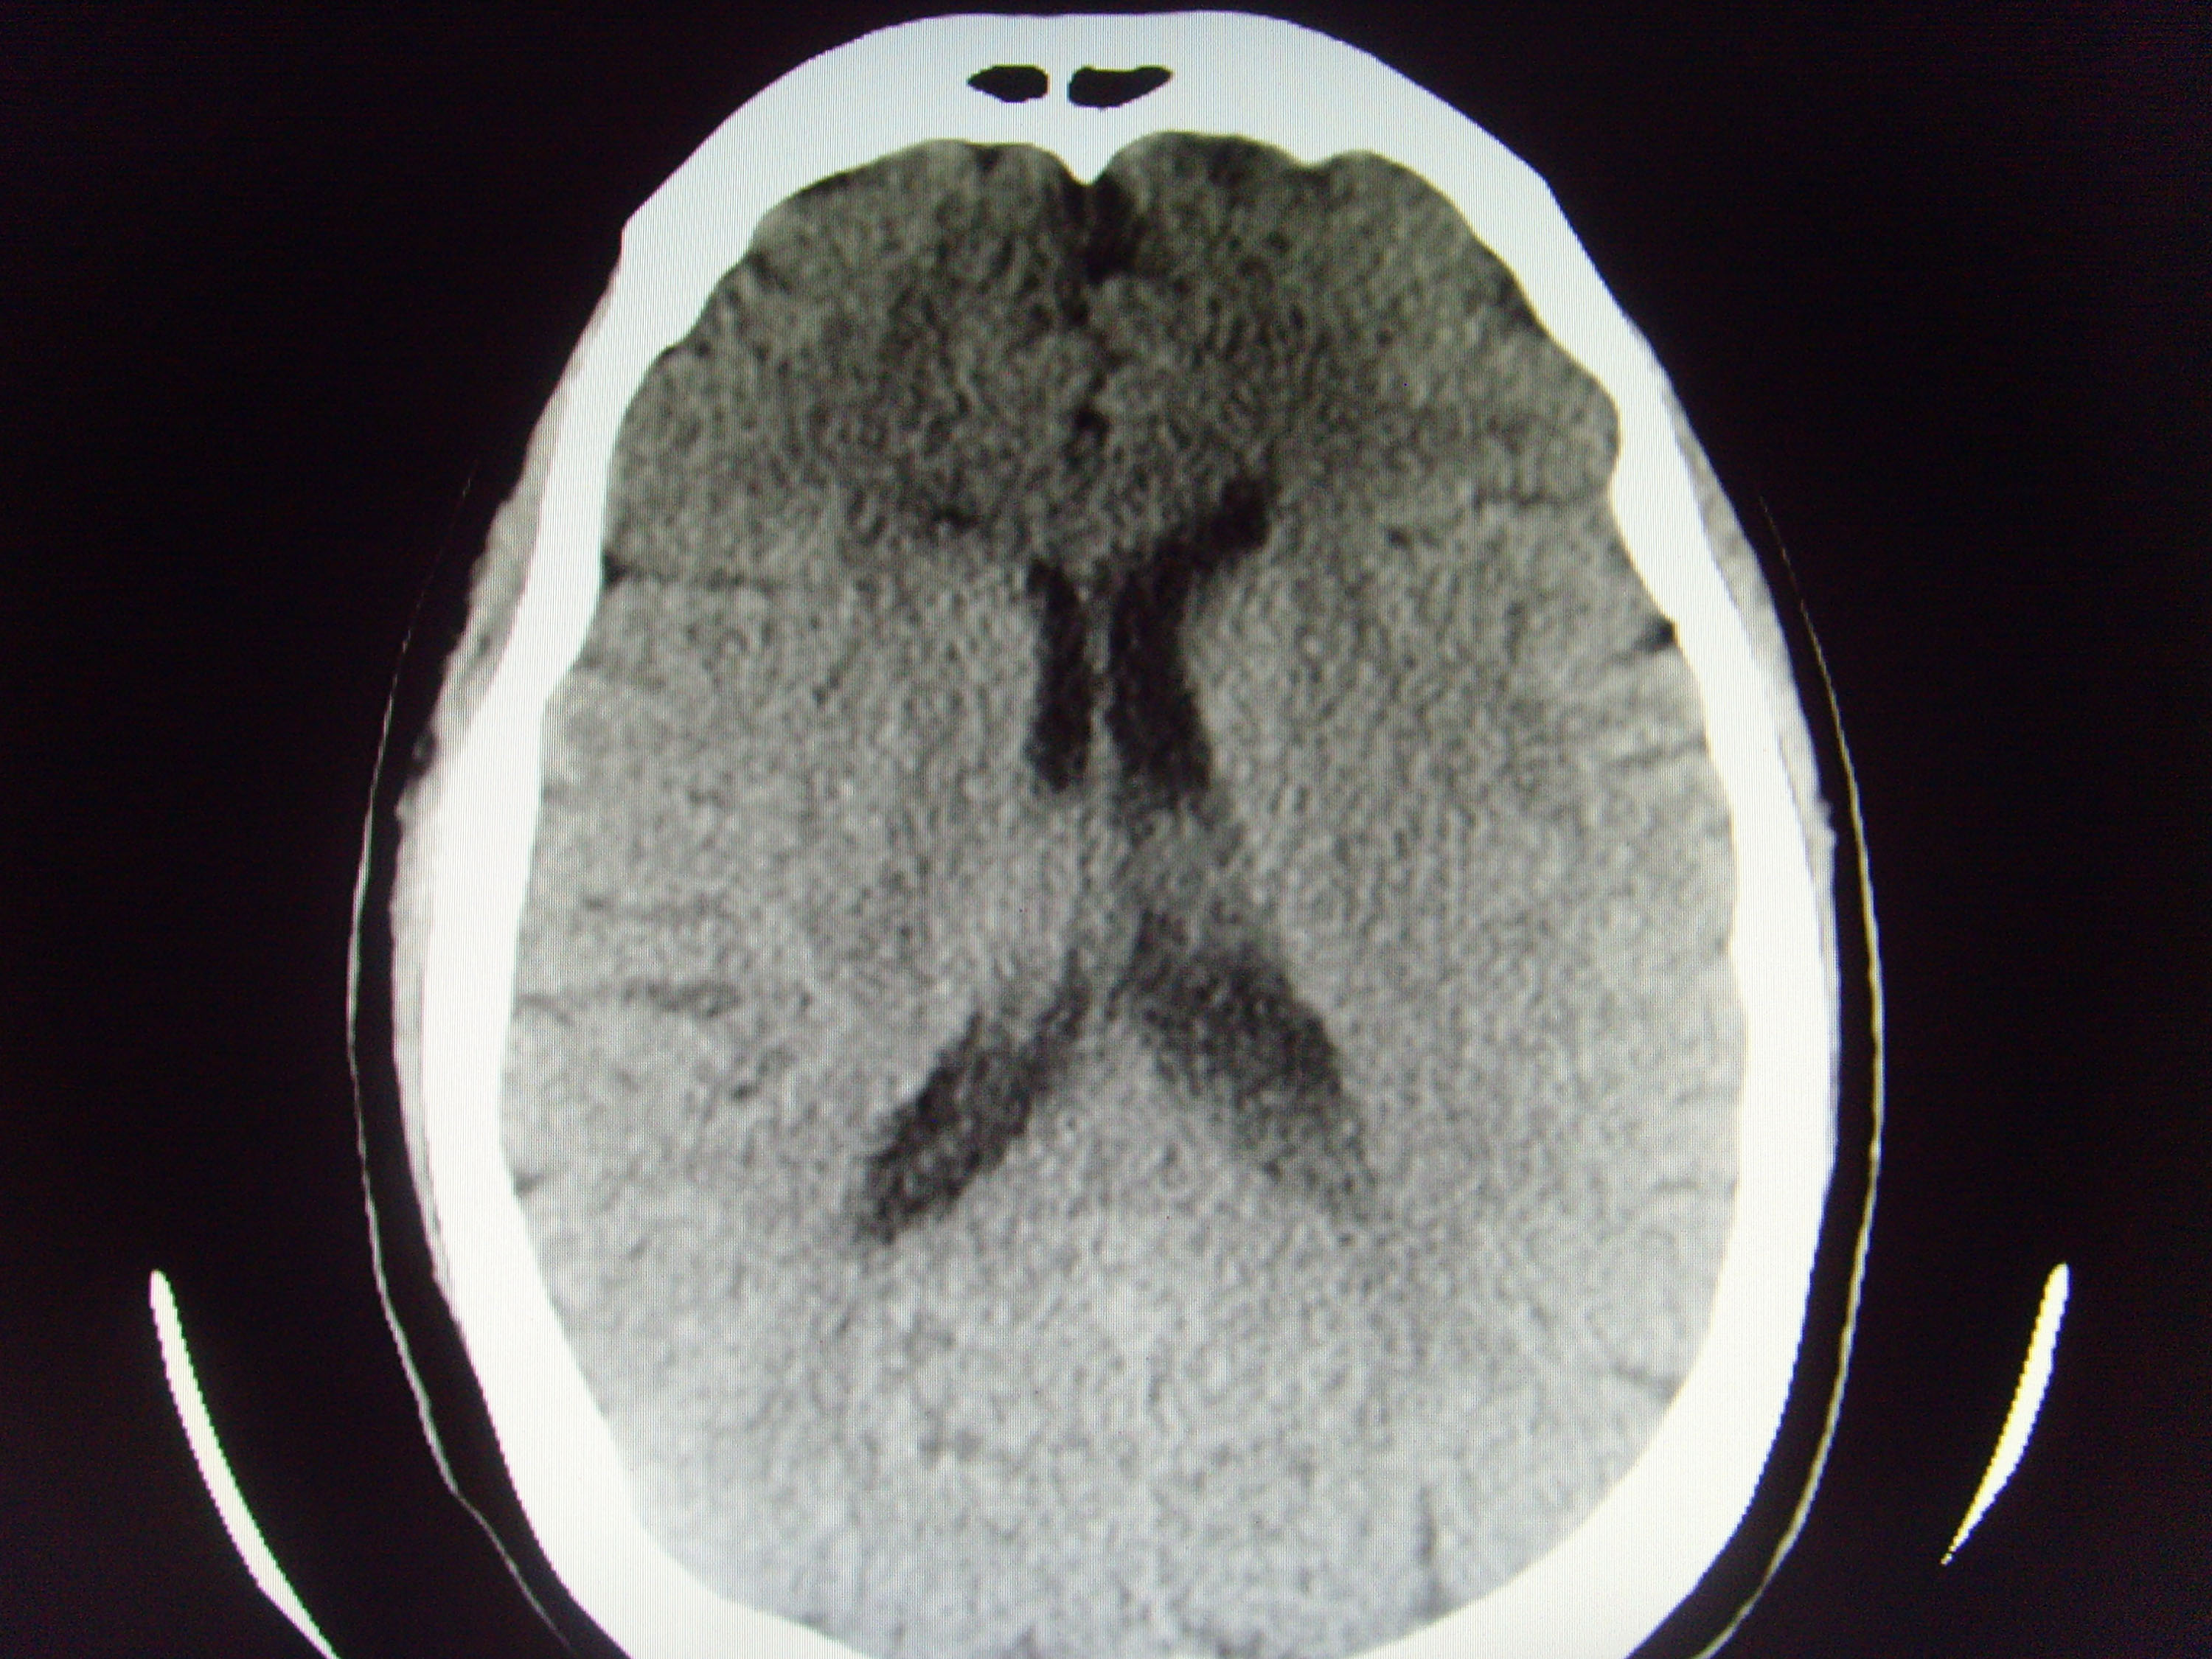

CT52503:左侧顶部什么病变?

左侧顶部什么病变?

考虑:左侧镰旁脑膜瘤、

考虑左侧镰旁脑膜瘤

考虑左侧镰旁脑膜瘤;建议:行CT增强扫描或MRI检查。